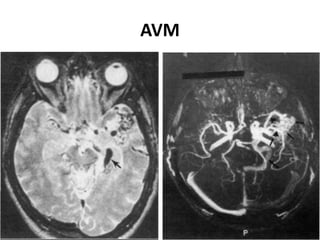

 Secondary role to digital subtraction angiography.

 The typical AVM appears on spin-echo MRI as a cluster

of focal round lesions or serpentine areas of signal void

 3D CE MRA is superior to 3D TOF MRA and equivalent to

subtraction angiography in 70-90%of cases in depicting

AVM components.

A-V Malformations

AVM